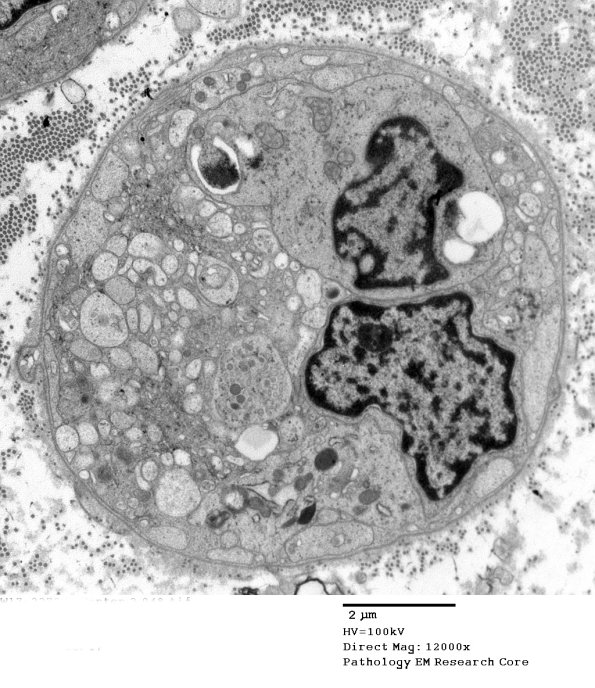

2C1,2 Without immunohistochemistry it is difficult to determine the cell type within the original basement membrane; however, most likely they are Schwann cells. The vacuoles include Schwann cell cytoplasm and probable axoplasm. Where is the myelin debris? It is possible that this degenerating collection of organelles and debris was generated from an unmyelinated axon.